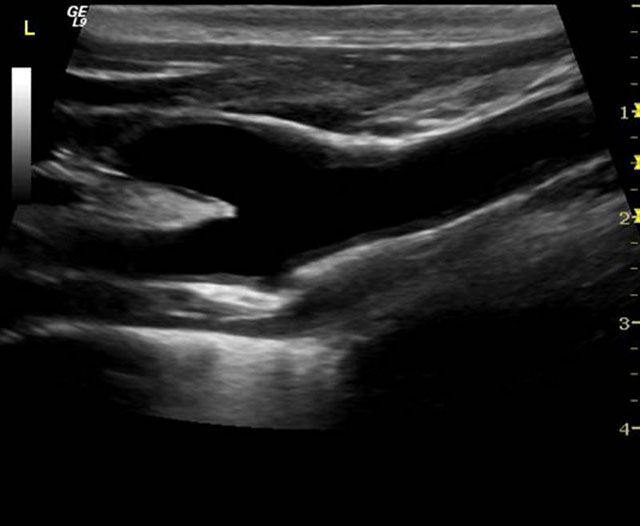

• Μαστού

Η τεχνολογία Matrix που ενσωματώνεται στην ηχοβόλο κεφαλή M12L επιτυγχάνει εστίαση και επεξεργασία της υπερηχογραφικής εικόνας σε τρεις διαστάσεις, για υψηλή ακρίβεια τομής, ευκρίνεια και ποιότητα εικόνας στις εξετάσεις μαστού, θυρεοειδούς και λοιπών επιφανειακών οργάνων.